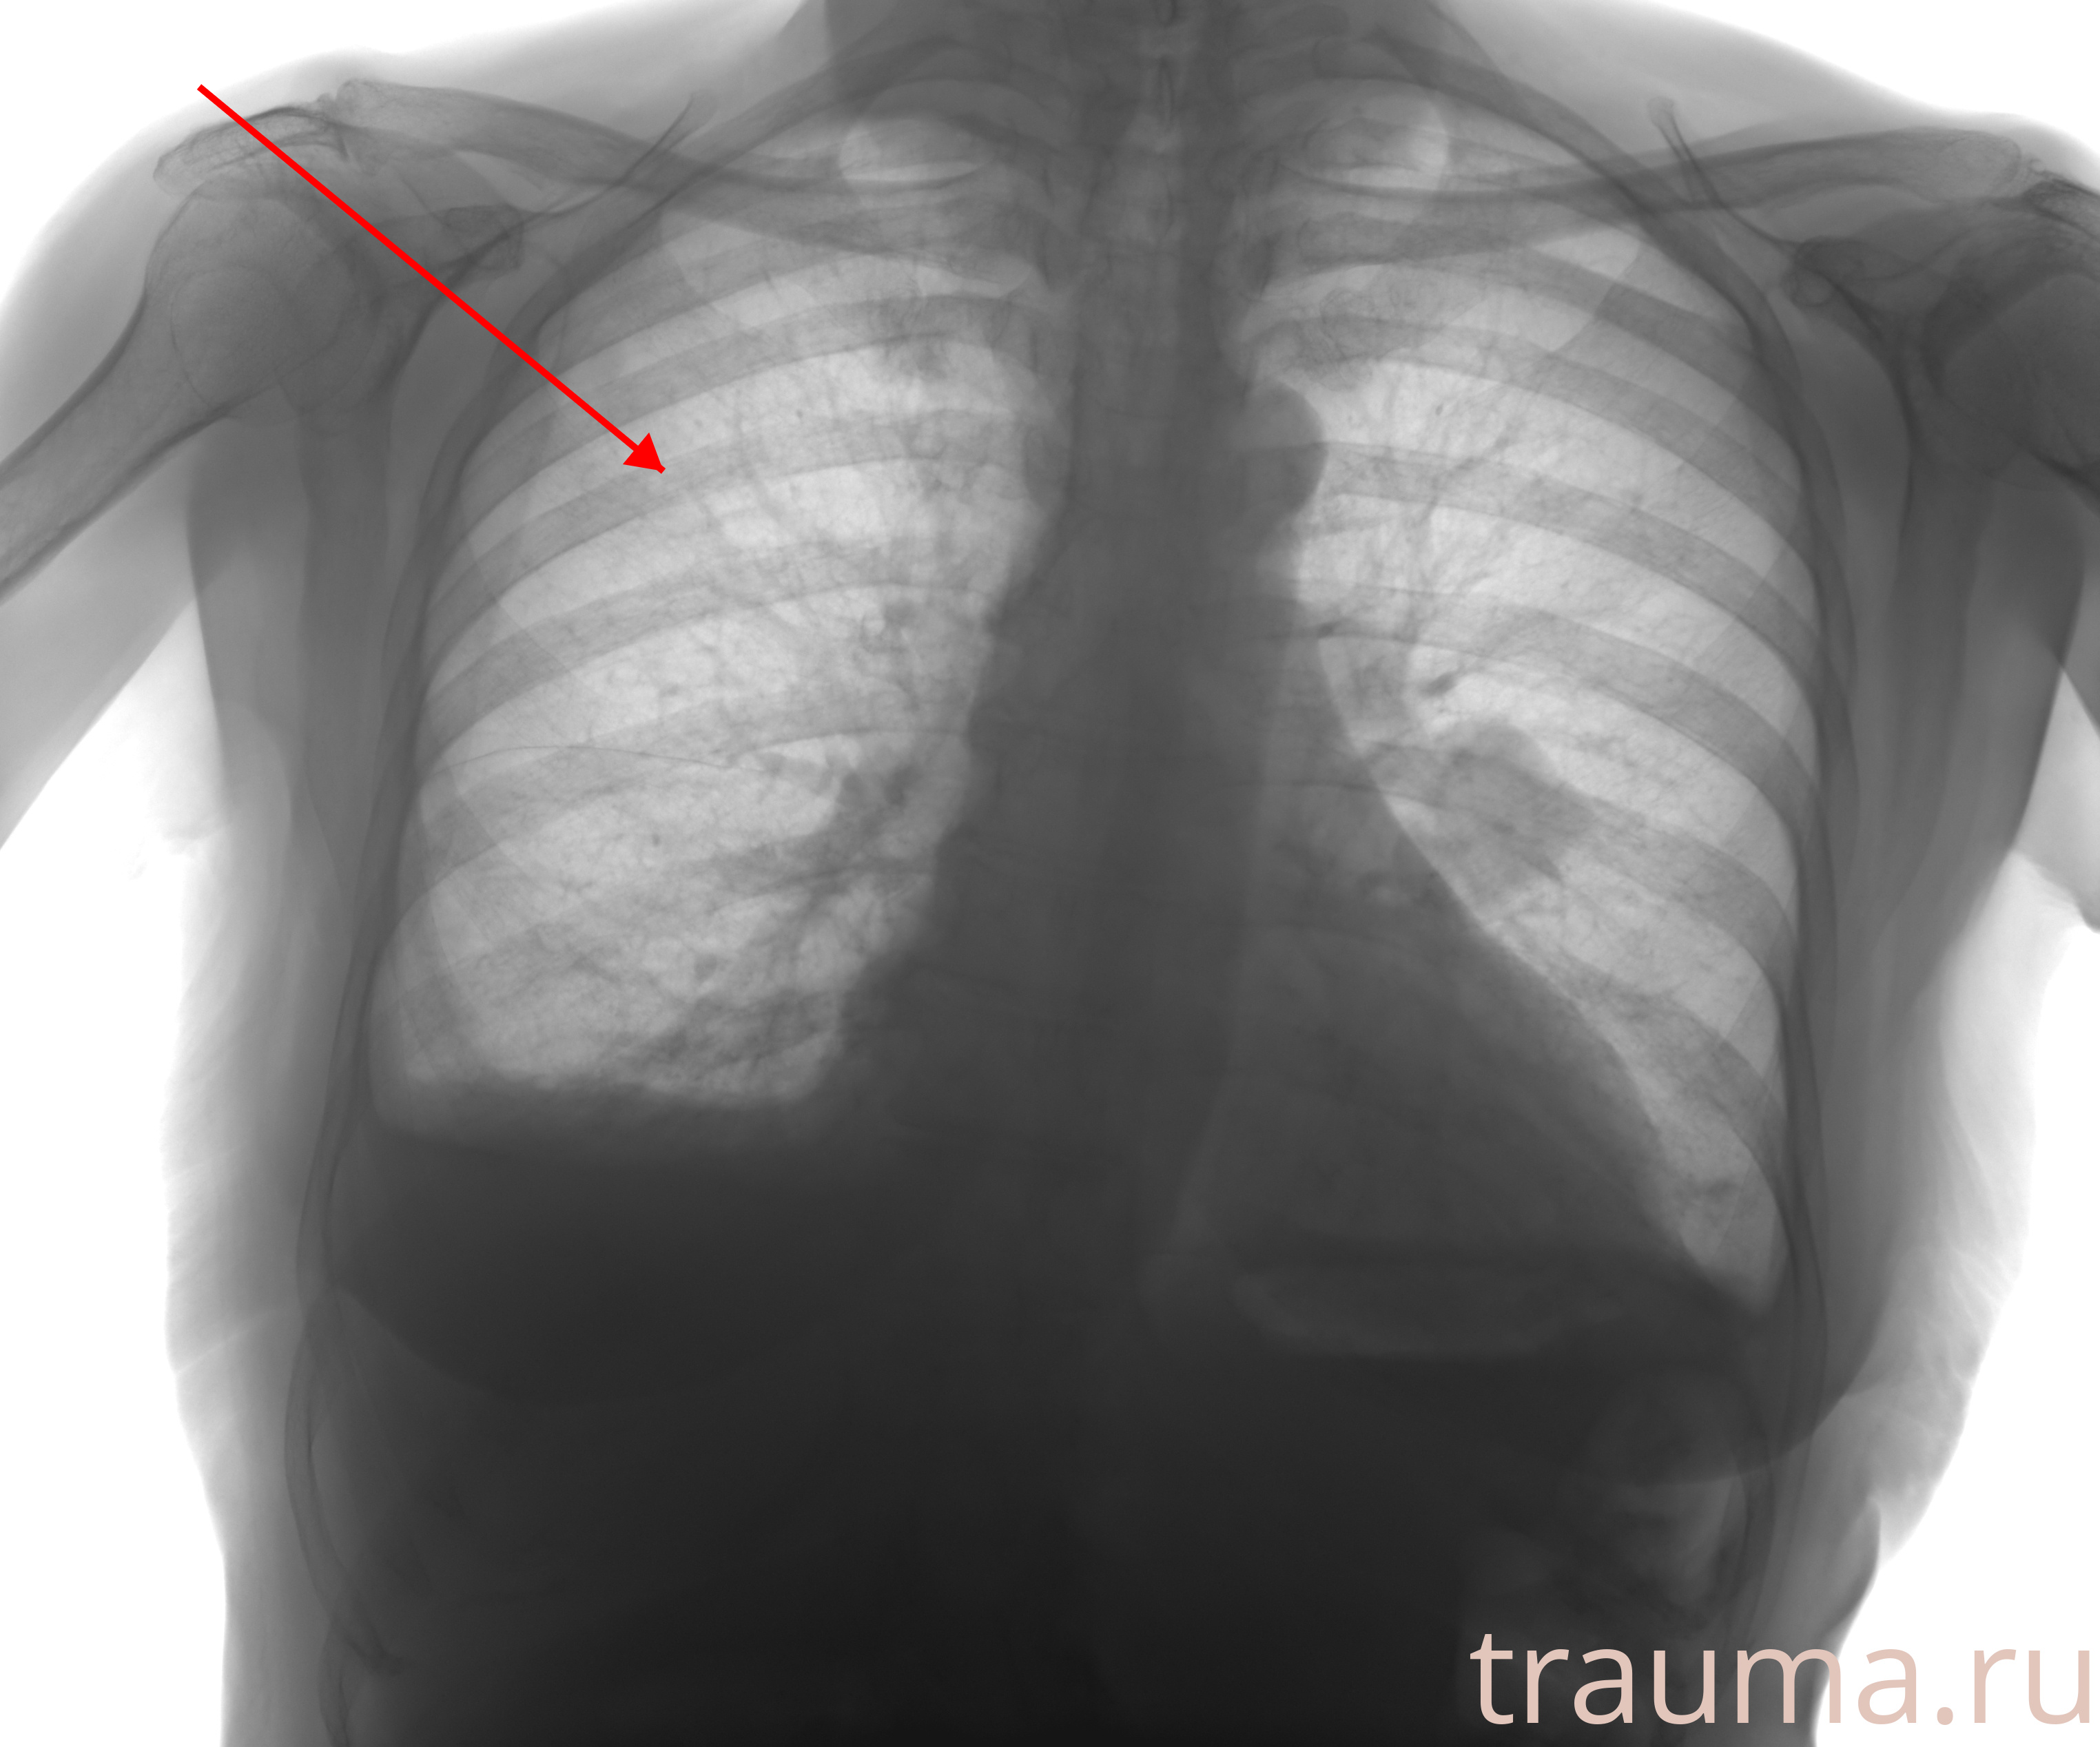

Рентгенограммы

Натуживание 26.12.2025 21:16:34